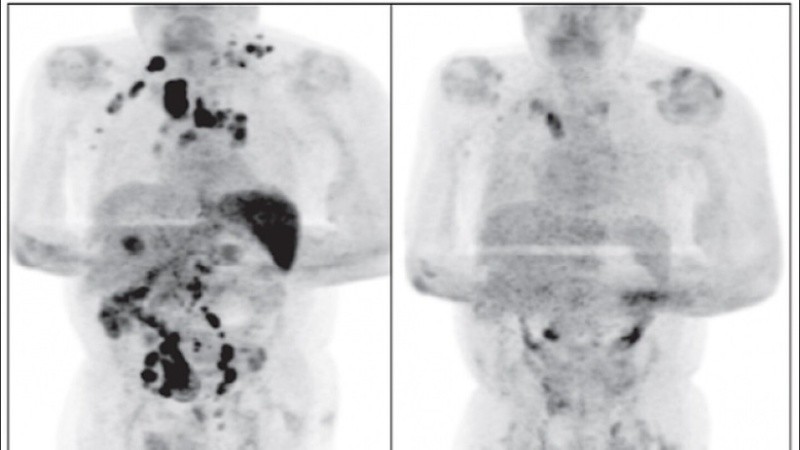

Cuatro meses después la inflamación de los ganglios se había reducido y una exploración por tomografía reveló una remisión generalizada del linfoma, a pesar de que no se le administró corticosteroides ni inmunoquimioterapia, aclara el informe.

Según los autores que dieron a conocer este caso, la hipótesis es que la infección por sars-cov-2 desencadenó una respuesta inmunitaria antitumoral, algo que, según señalan los especialistas, se ha descrito con otras infecciones en el contexto del linfoma no Hodgkin de alto grado.